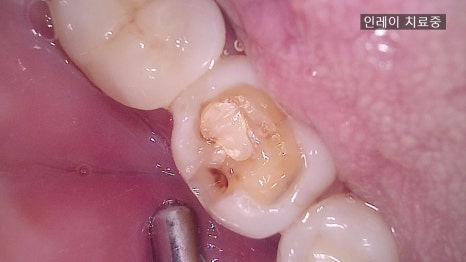

① 충치 제거 및 치아 삭제

– 충치 부위를 제거하고 인레이가 들어갈 자리를 정밀하게 다듬습니다.

③ 인레이 제작

– 원내 기공실에서 환자분 치아와 동일한 색상, 형태로 세라믹 인레이를 제작합니다.